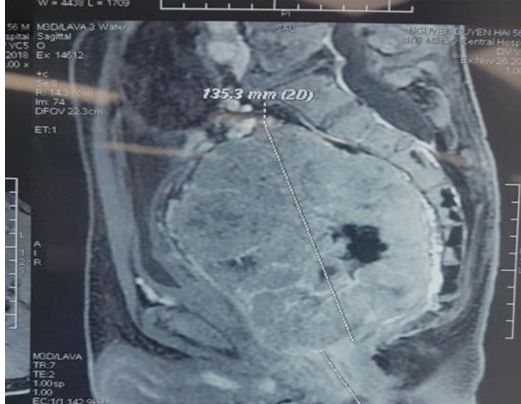

Phẫu thuật cắt bỏ thành công khối u trực tràng kích thước lớn ảnh 1Hình ảnh chụp khối u của bệnh nhân. (Ảnh: PV/Vietnam+)

Qua thăm khám và đánh giá trên phim chụp cắt lớp vi tính, các bác sỹ nhận thấy cách mép hậu môn 3cm có khối u khổng lồ GIST trực tràng bề mặt sần sùi, mật độ chắc, chiếm hết lòng trực tràng, không di động.

Kíp bác sỹ Khoa Phẫu thuật hậu môn trực tràng đã thực hiện phẫu thuật cắt bỏ khối u trực tràng với kích thước 5,5cm x 13,5cm.